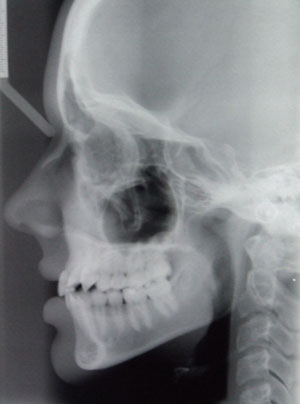

Distinctive dysgnathia – faulty positioning of the teeth – requires orthodontic treatment. For children and young people, it is advantageous to coordinate the treatment with the growth potential of the facial skull, in order to connect the corrective process of the treatment with the synergy of the natural growth process. For this purpose, removable orthodontic braces, adhesive connections with brackets attached to the teeth, and guide wires (multi-band treatment) are used to move the teeth into new positions in the jawbone. Adults, too, can have faulty tooth positions corrected. Lingual technology and the invisalign system provide the possibility of relatively invisible orthodontic treatment. Our office does not provide orthodontic treatment in-house; rather, we ascertain the need for such treatment and refer patients to competent providers. |